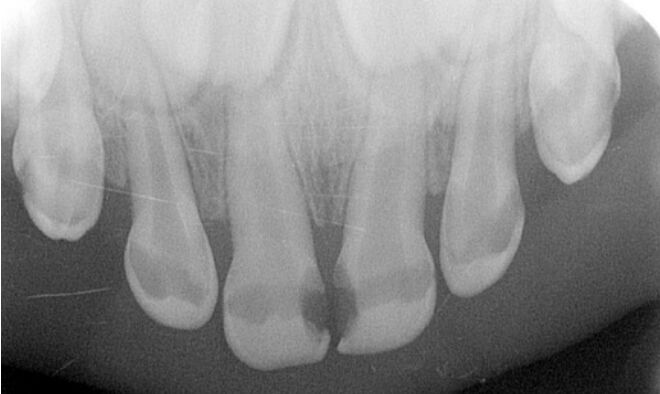

40.3歲男童半夜時常驚醒、母親多以親餵母乳安撫;一天多次吃巧克力當點心;因牙痛拍攝放射性影像如圖示,下列敘述何者正確?①上顎門齒可考慮直接覆髓術(direct pulp capping) ②上顎 門齒可評估裝置樹脂牙冠(strip crown)或預製型二氧化鋯牙冠(prefabricated zirconia crown) ③屬於嚴重早發性齲齒(severe early childhood caries),應改變點心的種類 ④母奶成分天然不易造成齲齒,不必強行戒除或改變哺乳習慣 (A)①③④ (B)①②③ (C)僅②④ (D)僅②③